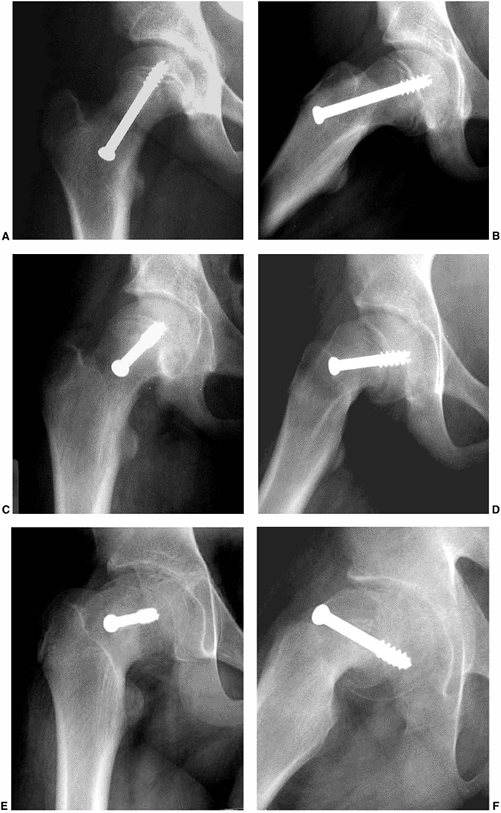

![]() |

Figure 26.4

A coronal section demonstrating vascularity of the proximal femur in a 13-year-old boy. Part of the vascular ring is visible at the base of the femoral neck, giving rise to the ascending cervical arteries which then enter the femoral head and supply blood to the superior head. (From Crock HV. A revision of the anatomy of the arteries supplying the upper end of the human femur. J Anat 1965;99:77–88, with permission.) |

has been well documented by Crock and subsequently by Chung (151,152) (Fig. 26.4).

Chung noted that these components are present in an individual at birth and persist without significant change into adulthood (151).